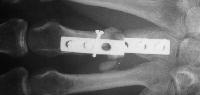

I removed this hardware, and used two mini condylar blade plates at right angles to resecure the distal bone juncture. This allowed more distal purchase while avoiding hardware placement beneath the metacarpal head extensor hood. I replated the proximal bone juncture although it looked clinically healed - not worth taking a chance.

Final result, eight months postop, healed:

Healed.